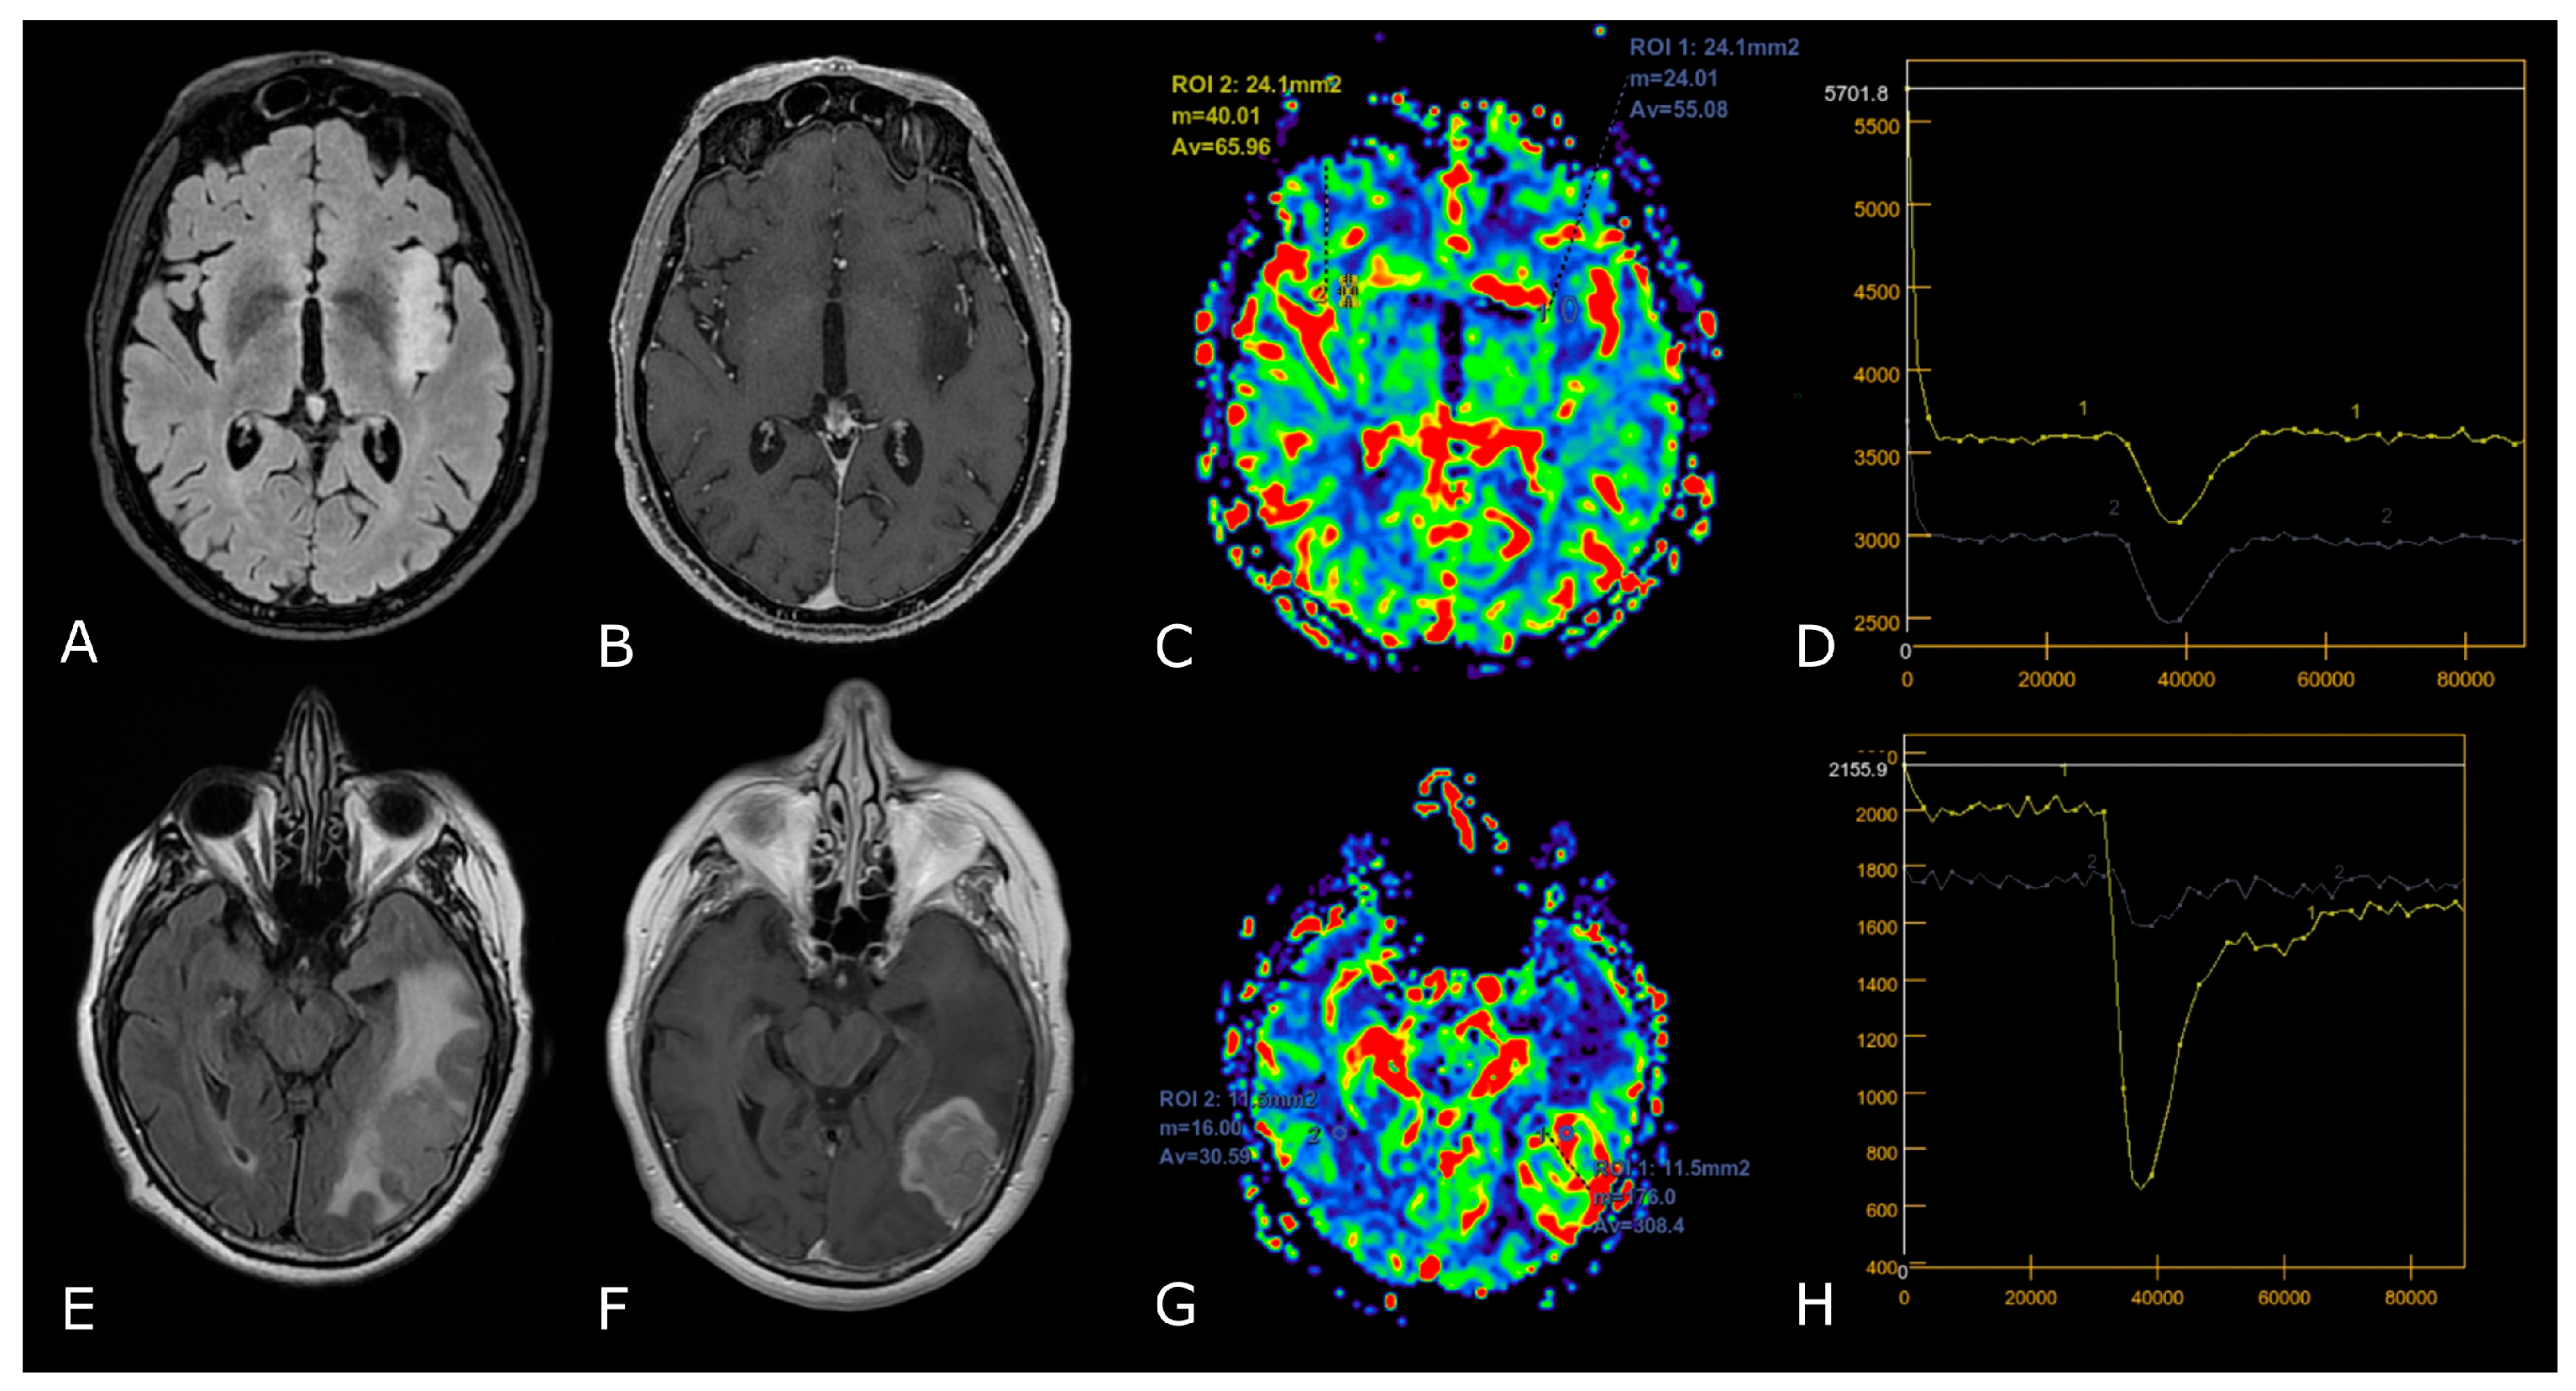

Figure 4.

DSC-PWI in differentiating HGG from LGG. Axial T2-FLAIR (A) and post-contrast T1w (B) of a low grade IDH-mut left insular astrocytoma. DSC-PWI demonstrates normal rCBV (C) and complete return to baseline of the signal-intensity-time curve (D). The second row shows axial T2-FLAIR (E) and post-contrast T1w (F) of a left temporal-occipital GB. DSC-PWI demonstrates increased rCBV (G) and reduction of PSR consistent with BBB breakdown (H).

3.2.1. Differentiating HGG from LGG and Clinical Prognosis

LGGs are mostly characterized by native vessel while the hypoxic angiogenic microenvironment of HGGs presents with an increased number of leaky vessels [23]. These features are reflected by increased microvascular proliferation and increased BBB permeability in more aggressive tumors. In fact, numerous studies have demonstrated DSC-rCBV and Ktrans to be consistently higher in HGGs. ASL-derived CBF has also been reported to be higher in HGGs [24,25]. K.M. Schmainda et al. reported DSC-rCBV of 1.4 to have sensitivity/specificity of 90/77% in distinguishing LGGs from HGGs [26]. However, several papers suggest different threshold values, so that no clinically useful threshold values are currently available (Figure 4) [27,28].

The differences between PsP and radiation necrosis (RN) are related both to the timing of presentation, i.e., 3–6 months for PsP and 1 year after RT in RN, but also to the different pathophysiology whereby RN presents as permanent damage to the brain tissue, necrosis, and vascular thrombosis [35,36,37]. Many DSC studies have shown that CBV is lower in areas of RN or PsP than in those of tumor progression. DCE studies are less numerous but have shown that patients with PsP and RN had significantly lower Ktrans values than patients with tumor progression (Figure 5) [23,29,30,31,35,36,37]. Studies focusing on PsP or RN specifically using ASL are scarce, but one study confirmed that the normalized ASL-CBF ratio was significantly higher in tumor progression than in radiation injury [38].

Figure 5.

Post-treatment changes vs. disease progression. (A–H): axial 3D-FSPGR post-contrast T1w images (A,E) and T2w images (B,F) with corresponding DSC-CBV (C,D) and DCE-Ktrans perfusion maps (G,H) of two IDHwt GBs 1 year after treatment (surgery and radio-chemotherapy). In the left panel the enhancing tissue shows low DSC-CBV and DCE-Ktrans, consistent with post-treatment changes. In right panel the enhancing tissue shows areas of increased DSC-CBV and DCE-Ktrans, suggesting disease progression.